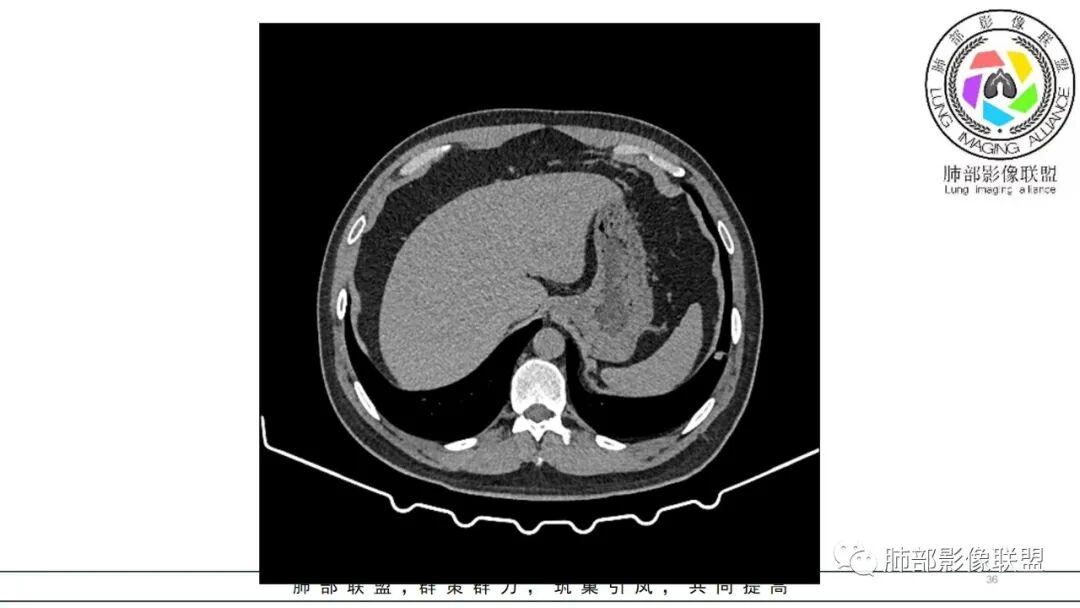

中年男性,咳嗽咳痰低热三天。右肺中叶、下叶条片状高密度影,局部边缘有晕,可见卫星灶。双肺另见多发小结节。考虑炎性肉芽肿,PC,鉴别GPA

中年男性,咳嗽咳痰伴发热3天,有鼻窦炎、 中耳炎病史,血沉、 CRP 增高,中性粒稍高。

双肺多发实性小结节,边清,多位于胸膜下。右肺中叶不规则实变影,沿支气管血管束走行,似有跨叶。

此病例临床与影像比较割裂,难以统一。可能疾病谱:GPA,隐球,结核,NTM,肺癌并转移。

中年男性,咳嗽咳痰发热,鼻炎中耳炎,血沉高,右肺中叶条状高密度实变影,边界清楚 ,双肺散在小结节,部分小空洞,首先考虑GPA,鉴别结核

男,47岁,咳嗽咳痰发热三天,既往中耳炎病史。CT示双肺多发随机分布小结节,多位于胸膜下,部分伴小空洞,右肺中页不规则实变影,沿支气管血管束走行。实验室检查血沉,CRP增高。综合考虑为感染性病变,隐球可能,鉴别GPA

双肺多发结节,以胸膜下分布为主,形态相似,边缘较规整,少部分边缘晕征,无分叶毛刺;右肺中下叶多结节融合并实变影,边缘平直、U形征,跨叶。

病灶与支气管血管束无关,定位肺实质来源病变,考虑良性病变,炎性肉芽肿病变:隐球可能。

急性起病,中耳炎病史,右中叶病灶呈蠕虫样,跨叶生长,水平裂牵拉移位,两肺胸膜下多发结节灶,血道来源,病史支持感染性,没有免疫抑制,无咯血不支持曲霉及血管炎,急性病史也不支持TB,右中叶病变呈蠕虫样,有点小细胞癌的征象,但小c转移常见的是肺门和纵隔,本例也不支持,综和考虑支持炎性肉芽肿GPA,鉴别PC

中年男性,咳嗽咳痰低热3天,偶有血痰。有鼻炎、中耳炎病史。右中叶病灶呈指套样,跨右下叶,叶间胸膜牵拉移位。两肺胸膜下多发结节灶,边缘模糊见晕征,部分呈空洞结节。白细胞计数及CRP、血沉稍高。跨叶的指套样病灶有小细胞肺癌的影像特点,两肺多发结节,但近肺门、纵隔无肿大淋巴结,不符合小细胞肺癌的转移特点,考虑非肿瘤病灶。没有典型的多形态、未见树芽征,肺结核可能性小;两肺胸膜下病灶有晕征,存在隐球菌病可能,但右中下叶的主病灶形态在隐球菌病中罕见;有鼻炎病史,肺内病灶存在血管炎可能;患者为银行职员,应该经常接触纸币,有血痰症状,主病灶呈指套样,两肺多发晕征及空洞,存在曲霉菌感染可能。综上考虑肺曲霉菌病可能,鉴别血管炎、PC、TB。